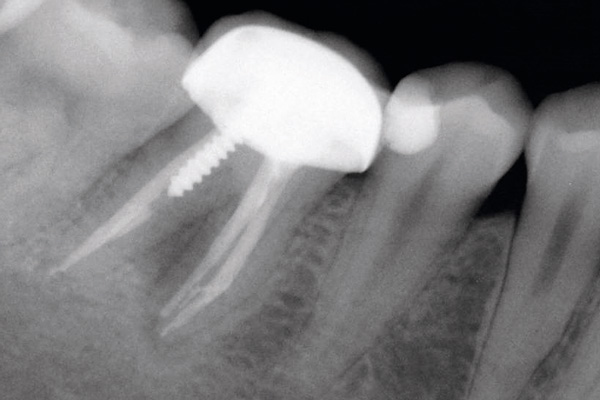

Socket preservation with permamem® and maxgraft® granules - Dr. P. Di Capua